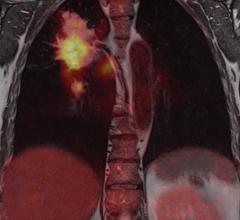

Contrast media, also called contrast agents, are used to enhance the blood and perfusion in tissues. This includes iodine based contrast for on computed tomography (CT), gadolinium based agents for MRI and lipid bubble contrast agents used in ultrasound.

Contrast agents improve every kind of medical image from computed tomography (CT) to magnetic resonance imaging (MR) ...

The medical imaging market relies heavily on contrast media, injected into patients to increase the contrast of bodily ...